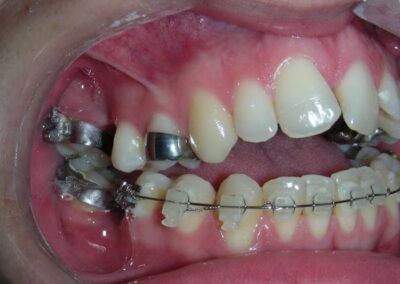

The vertical vector of intrusion was located too far posteriorly to allow for the placement of TADs in that region. At this point, the utility arch developed by Dr. Ricketts was introduced into the mechanics . I referred to as the “Tilting Utility Arch.” made with Blue Elgiloy .017″ × .025″. It was employed as a lever arm to transmit the intrusive force generated by the coil spring and anchored by the TADs.

The upper brackets were bonded solely for the purpose of providing stability to the utility arch . Following the hierarchically structured treatment plan, we proceed with the alignment and leveling phase in order to enable mesialization of the posterior segments using sliding mechanics, which works effectively in conjunction with Roth prescription brackets .022.

A progressive archwire sequence was used for alignment, leveling, and three-dimensional control.

- .018″ × .018″ Blue Elgiloy sectional archwire was placed in three segments in the maxillary arch to maximize the effectiveness of Class II intermaxillary elastics, in conjunction with space closure (mesialization) in the mandibular arch.

- 017″ × .025″ Blue Elgiloy sectional leveling archwire beetwen # 35-37 and 45-47

- 017″ × .025″ Stainless Steel (SS) + Closed-coil NiTi springs were activated between the molars and anterior segment

- 019″ × .025″ Stainless Steel (SS)

After two years of treatment using appropriate biomechanics, the overbite was successfully corrected from -8 mm to +1 mm, achieving complete closure of the anterior open bite without exacerbating the patient’s lower facial third vertical proportions. At this stage, occlusal contacts were verified using articulating paper, and functional movements of the canines and incisors were evaluated to ensure proper anterior guidance and disclusion patterns. The patient was then referred to speech therapy (myofunctional evaluation) as part of the pre-debond assessment protocol.